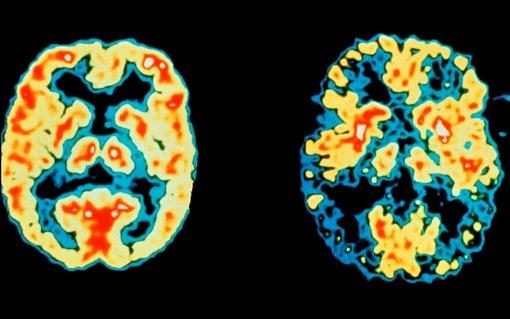

اما 15 درصد از 891 بیماری که هیچ داروی دیگری مصرف نمیکردند، نتایج جالبی را نشان دادند. این افراد علاوه بر اینکه مهارتهای اساسی شناختی آنها طی 18 ماه کارآزمایی حفظ شده بود، مناطق اصلی مغزشان تا یک سوم کمتر از سایر شرکتکنندگان کاهش یافته بود.